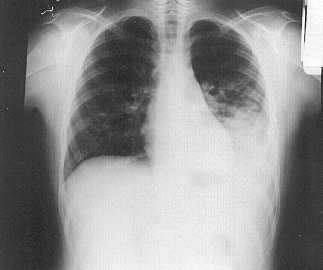

Em pneumonia adquirida na comunidade, é necessária a realização de algum exame complementar? Para confirmar o diagnóstico deve-se realizar um Raio-X de tórax.